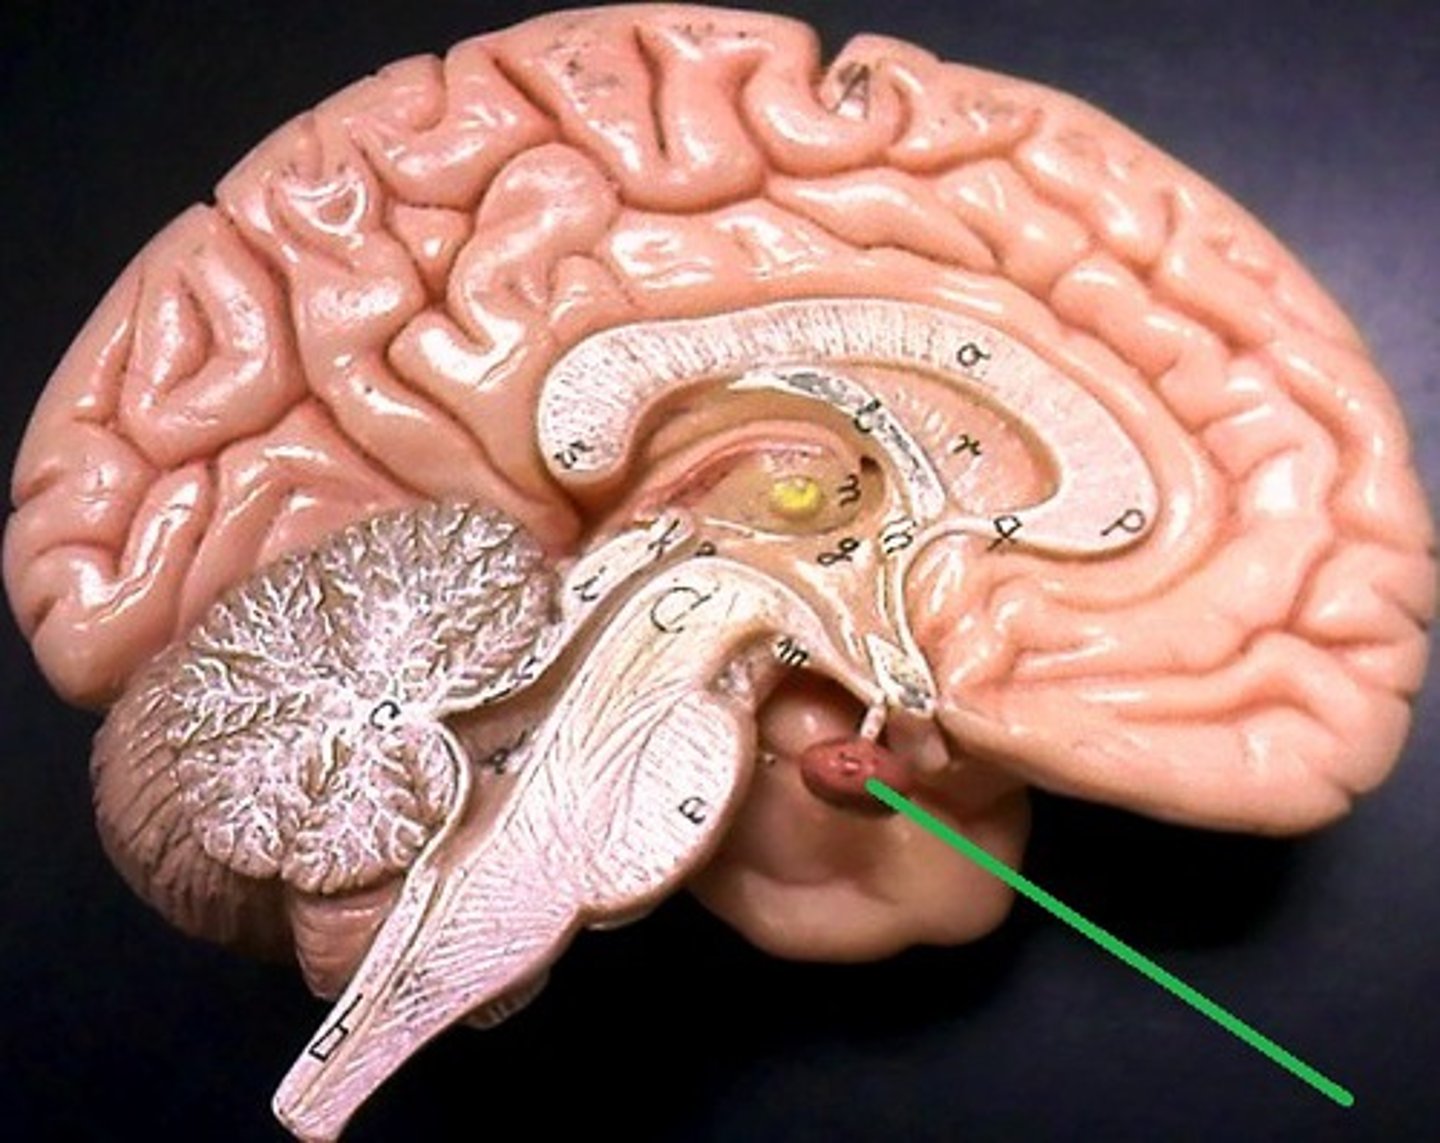

corpus callosum

septum pellucidum

fornix

parietal-occipital fissure

thalamus

hypothalamus

intermediate commissure

optic chiasma

pituitary gland

pineal gland

cerebral peduncle

superior colliculi

inferior colliculi

pons

cerebellum

arbor vitae

cerebral aquaduct

fourth ventricle

medulla oblongata

midbrain